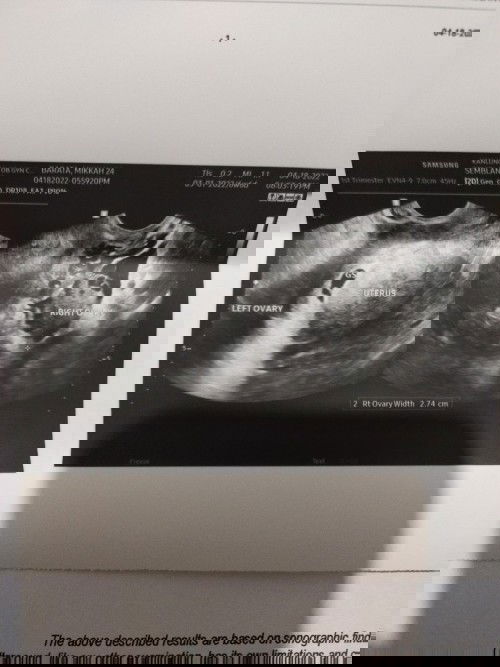

5 weeks 6 days ultrasound

Hi mommies! Ask ko lang if may same sakin na gestational sac pa lang ang kita sa scan at 5weeks and 6 days based sa tvs? May reseta din si ob ng aspirin dahil sa history ko ng miscarriage and duphaston dn para pangpakapit. Ob said no need to worry naman daw since super early pa naman daw ni baby, pero gusto ko magkaron ng peace of mind